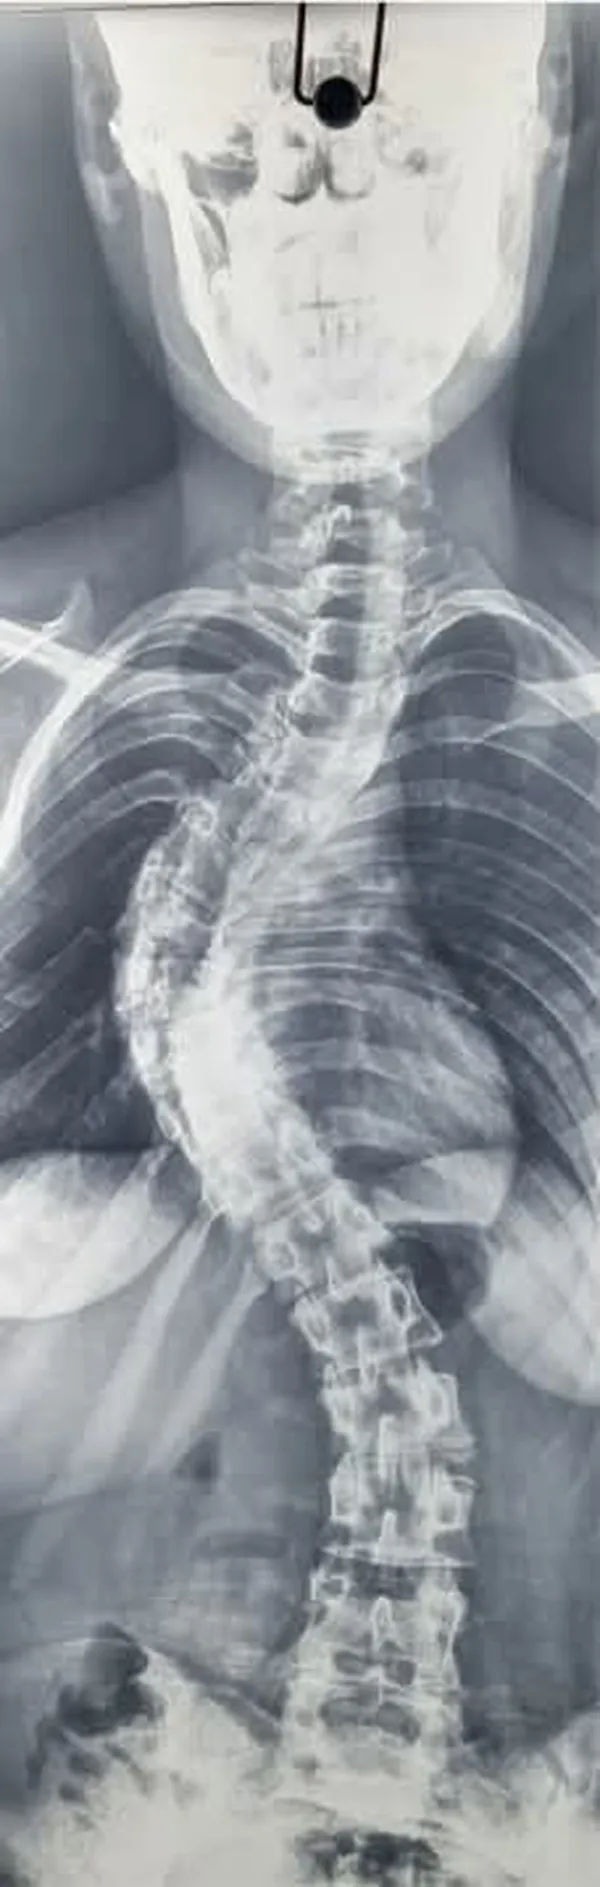

جانب من العملية الجراحية

جانب من العملية الجراحية جانب من العملية الجراحية